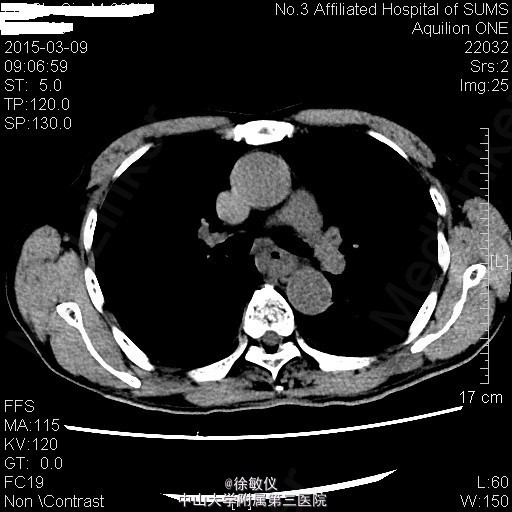

老年男性,主诉:进行性吞咽困难1月 现病史:患者1月前无明显诱因出现吞咽梗阻感,以进食粗糙、过热食物时明显,进食半流质症状不明显,10天前就诊外院行胃镜检查提示:食管癌,活检病理"鳞状细胞癌"。

查体:无特殊。 胸部CT平扫+增强:中段食管癌,部分层面与胸主动脉分界欠清;纵隔多发小淋巴结。